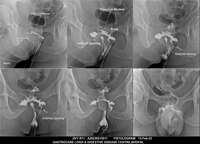

Section: FISTULOGRAM Total: 8 images

BaM Enteroclysis Loopogram BaE Fistulogram Urethrogram HSG